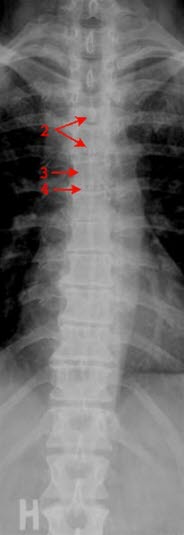

Normalt frontalbilde av thoracalcolumna (ryggsøylen i brysthøyde)

- Processus spinosus

- Virvelcorpus

- Mellomvirvelskive